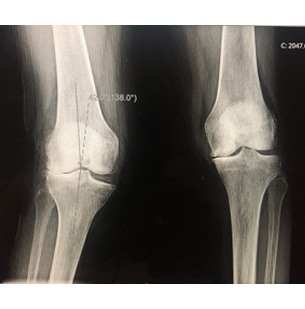

80 something year old with severe values (knock-knee) arthritis losing ability to walk and and in severe pain.

Robotic assisted, cemented total knee performed with straightening of leg deformity and significant pain reduction.

Before

After